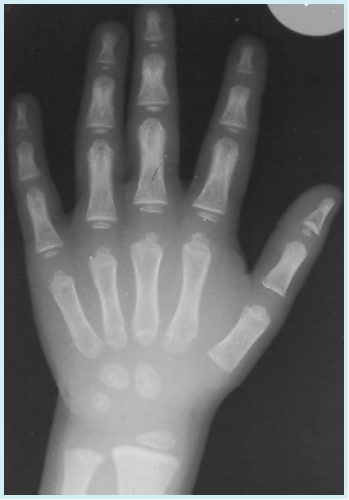

骨 龄

▪ 左手正位片

▪ 落后生理年龄2岁以上

8岁患儿

腕部骨化中心:4枚

骨龄:3岁+